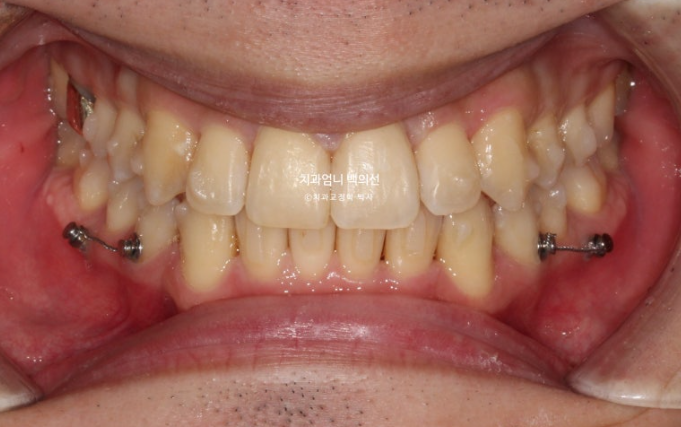

25.03

치료 후 중심선은 완벽하게 맞습니다.

1급 교합관계가 드디어 달성되었다는 전제 하에 (교합관계조차도 엉망인데 교합이 안 좋게 끝난다는 상황은 제외하겠습니다.) 사진과 같이 위아래 어금니가 약간 뜨는 현상이 생깁니다.